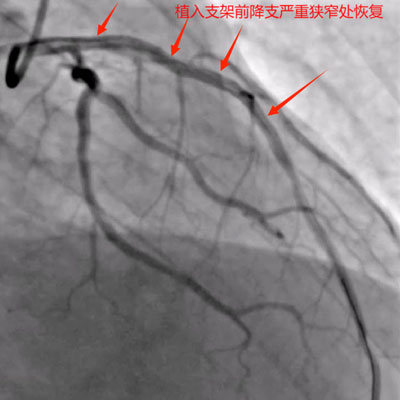

据了解,患者姓钟,男性,58岁,长期抽烟,4月20日因活动后胸痛2天于李家河卫生院就诊,完善相关辅检后考虑心肌梗死,由120送入最近胸痛中心——来凤县人民医院。来凤县人民医院胸痛中心按胸痛救治流程收治入院,入院后行冠脉造影提示:三支病变,前降支弥漫性病变,开口狭窄最重约40%,近段狭窄最重约90%,中段狭窄最重约80%,远段狭窄最重约50%,第一对角支开口至近段弥漫性病变,狭窄最重约80%;回旋支开口正常,于钝缘支分又前狭窄最重约90%,远段弥漫性病变,狭窄最重约80%;右冠开口正常,中段狭窄最重约50%。

获得家属同意后,考虑到患者病变复杂,来凤县人民医院心血管内科介入团队为患者制定了详细手术方案,因病变特殊性左冠前降支及回旋支两支血管需同期处理,导致手术更复杂,对术者要求更高。术中前降支使用球囊封堵法保护住了成角很大的对角支,回旋支扭曲使用双导丝技术成功植入支架,经过2小时努力同期完美处理前降支及回旋支病变结束手术。